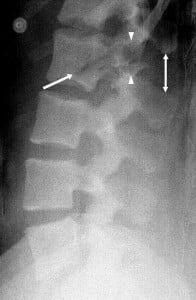

Some Radiographs

The following radiographs can give you and idea of what a chance fracture is and what is its location: